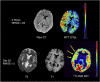

As a sequel of brain ischemia, selective neuronal loss (SNL)-as opposed to pannecrosis (i.e. infarction)-is attracting growing interest, particularly because it is now detectable in vivo. In acute stroke, SNL may affect the salvaged penumbra and hamper functional recovery following reperfusion. Rodent occlusion models can generate SNL predominantly in the striatum or cortex, showing that it can affect behavior for weeks despite normal magnetic resonance imaging. In humans, SNL in the salvaged penumbra has been documented in vivo mainly using positron emission tomography and (11)C-flumazenil, a neuronal tracer validated against immunohistochemistry in rodent stroke models. Cortical SNL has also been documented using this approach in chronic carotid disease in association with misery perfusion and behavioral deficits, suggesting that it can result from chronic or unstable hemodynamic compromise. Given these consequences, SNL may constitute a novel therapeutic target. Selective neuronal loss may also develop at sites remote from infarcts, representing secondary 'exofocal' phenomena akin to degeneration, potentially related to poststroke behavioral or mood impairments again amenable to therapy. Further work should aim to better characterize the time course, behavioral consequences-including the impact on neurological recovery and contribution to vascular cognitive impairment-association with possible causal processes such as microglial activation, and preventability of SNL.